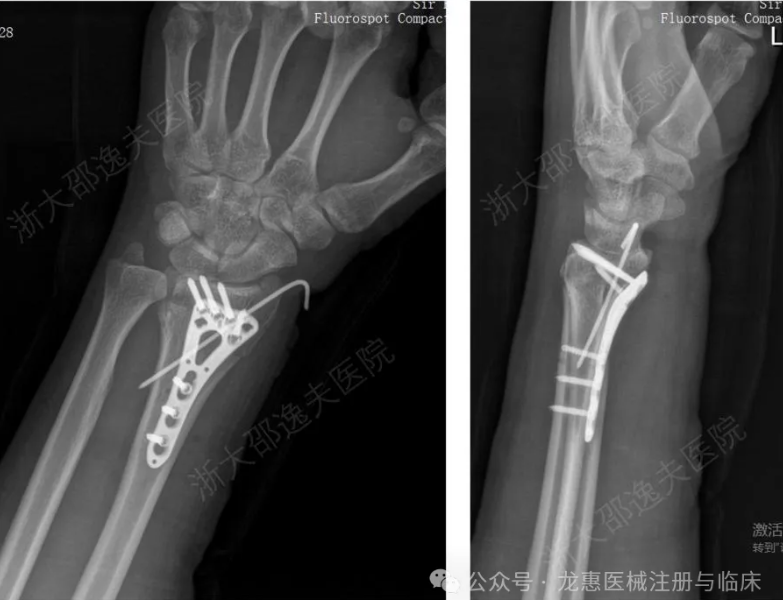

一位年轻工人因外伤导致腕部桡骨远端粉碎性骨折,传统治疗方案需大切口植入钢板螺钉,不仅创伤大、存在肌腱粘连或神经损伤风险,且需术后一年行二次手术取出。

桡骨远端骨折金属内固定治疗病例

应用“骨02”黏合技术,仅通过微创切口注入“胶水”材料,短短3分钟内即完成了粉碎骨块的精准黏合与固定。术后3个月随访显示,患者骨折愈合良好,无并发症,腕关节功能完全恢复